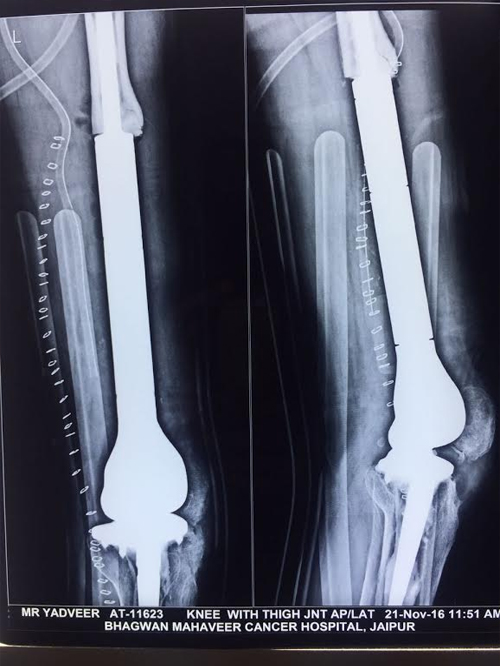

33 years old male k/c/o GCT Distal femur operated in 2009 elsewhere with megaprosthesis knee replacement. Presented with peri prosthetic fracture with implant fracture due to tribal trauma.

Revisions surgery done with removal of broken implants and weakened fractured bone pieces due to severe metallic reactions and reconstruction done with megaprosthesis

Patient is walking comfortably from next day of surgery